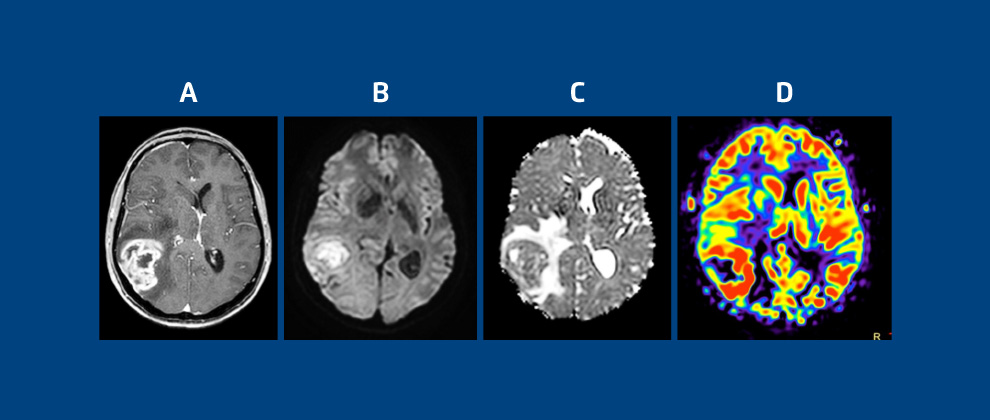

Figura 2: quadros A, B, C e D representam tumor de alto grau do SNC (glioblastoma).

O quadro A, em imagens em T1 com contraste, mostra tumor primário do SNC com realce irregular pelo contraste; quadros B e C, em Imagem por Difusão (DWI) e mapas de ADC, mostram restrição à difusão por alta densidade celular; quadro D, em perfusão cerebral ASL, sem contraste e mapa de CBF, mostra tumor bem vascularizado, com angiogênese tumoral.